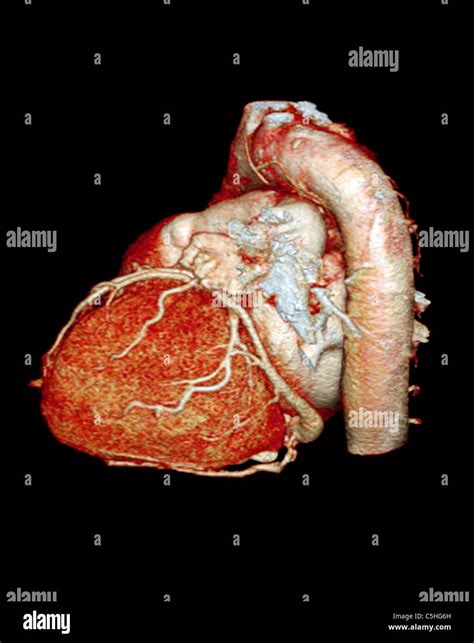

Cardiovascular health remains a top priority for medical professionals and patients alike, especially as diagnostic technology continues to evolve. When doctors need to get a clear, detailed look at the coronary arteries to assess the risk of heart disease, they often turn to advanced imaging techniques. A Ct Scan For Heart, clinically known as a Coronary Computed Tomography Angiography (CCTA) or a Coronary Artery Calcium (CAC) scan, has become a cornerstone in modern preventative cardiology. By providing high-resolution images of the heart's structure and its surrounding blood vessels, this non-invasive procedure allows physicians to identify potential blockages or calcification long before a patient experiences a major cardiac event.

The primary purpose of a Ct Scan For Heart is to evaluate the health of the coronary arteries. These vessels are responsible for supplying oxygen-rich blood to the heart muscle. Over time, these arteries can accumulate plaque—a buildup of fat, cholesterol, calcium, and other substances. If left unchecked, this plaque can harden or rupture, leading to restricted blood flow and an increased risk of heart attacks. Unlike traditional stress tests, which measure how the heart functions under pressure, a CT scan provides a direct visualization of the anatomy, allowing for a precise "map" of the arterial state.

• Coronary CT Angiography (CCTA): This scan utilizes an iodine-based contrast dye to highlight the interior of the arteries, allowing radiologists to see not only calcified plaque but also "soft" plaque that could potentially block blood flow.

Once the scan is complete, a specialized radiologist or cardiologist will analyze the hundreds of images produced to identify any narrowing of the arteries or presence of plaque. The results are typically compiled into a report that quantifies the extent of atherosclerosis. If your calcium score is high or significant blockages are found, your doctor will move from a preventative approach to an active management plan. This might include aggressive lipid-lowering therapies (such as statins), lifestyle interventions like specific exercise programs, or further invasive procedures if the blockage is deemed critical.